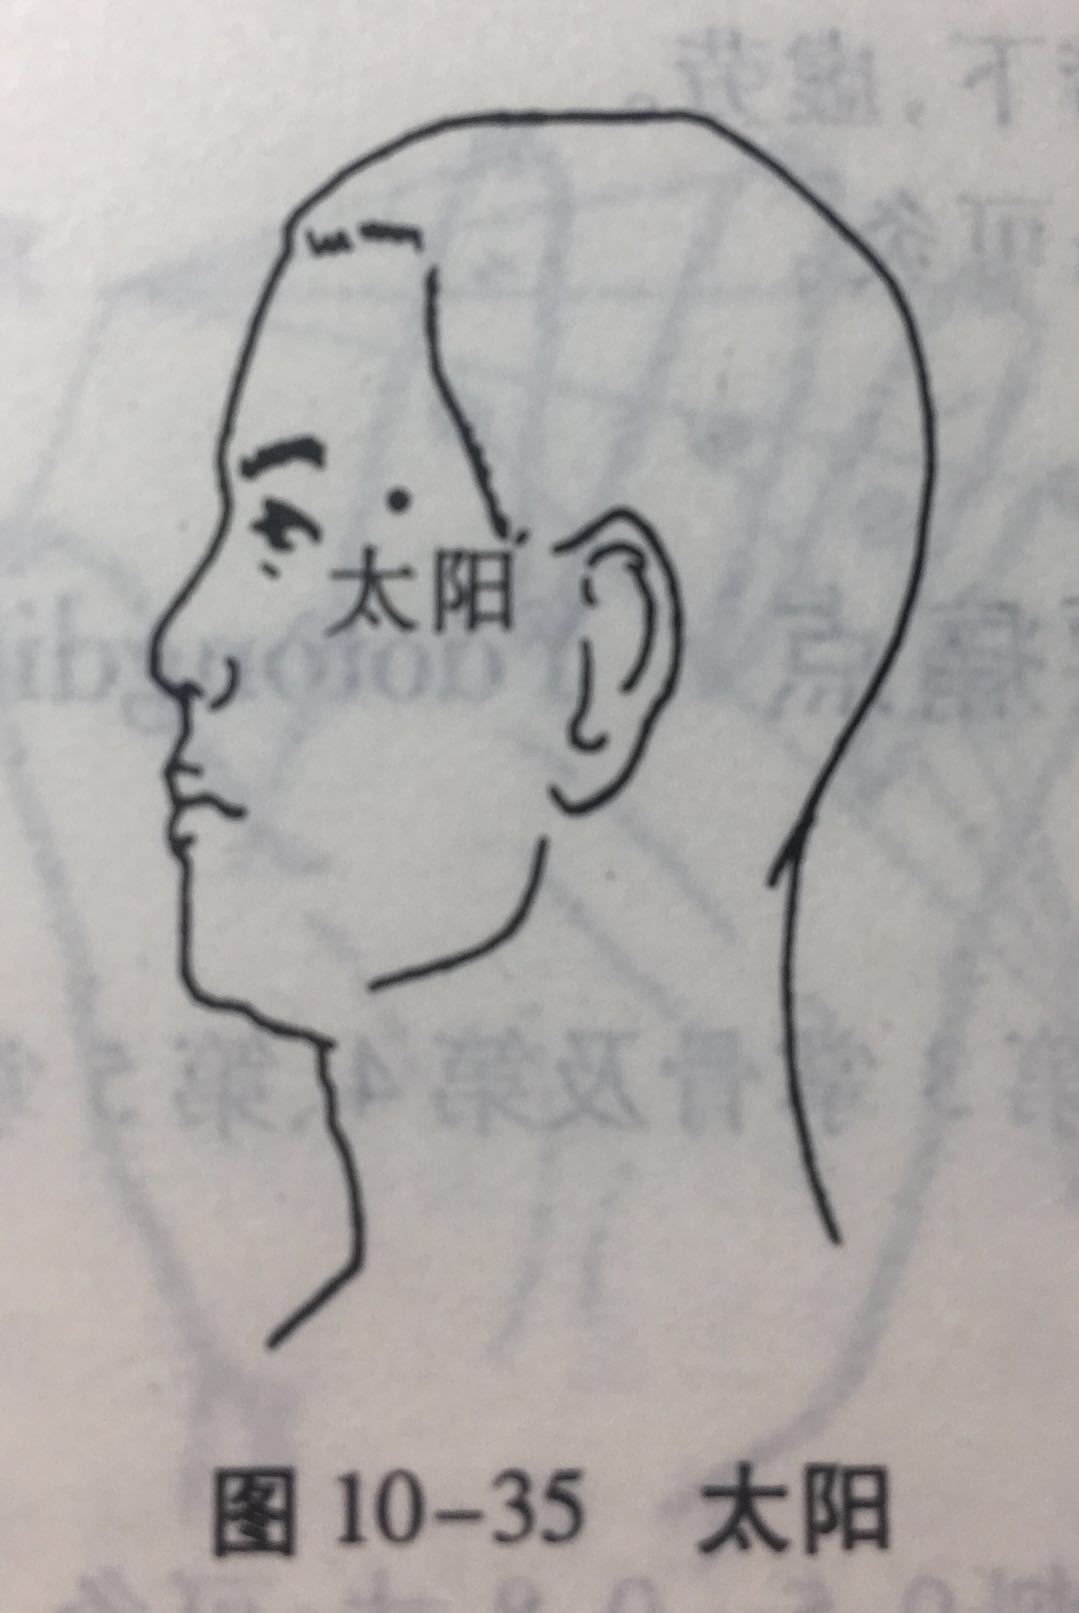

太阳

【定位】 在颞(niè)部,当眉梢与目外眦之间,向后约 1 横指的凹陷处(图 10-35)。

【主治】 偏正头痛,目赤肿痛,目眩,目涩,牙痛,三叉神经痛。

【刺灸法】 直刺或斜刺 0.3 ~ 0.5 寸;或用三棱针点刺出血。禁灸。